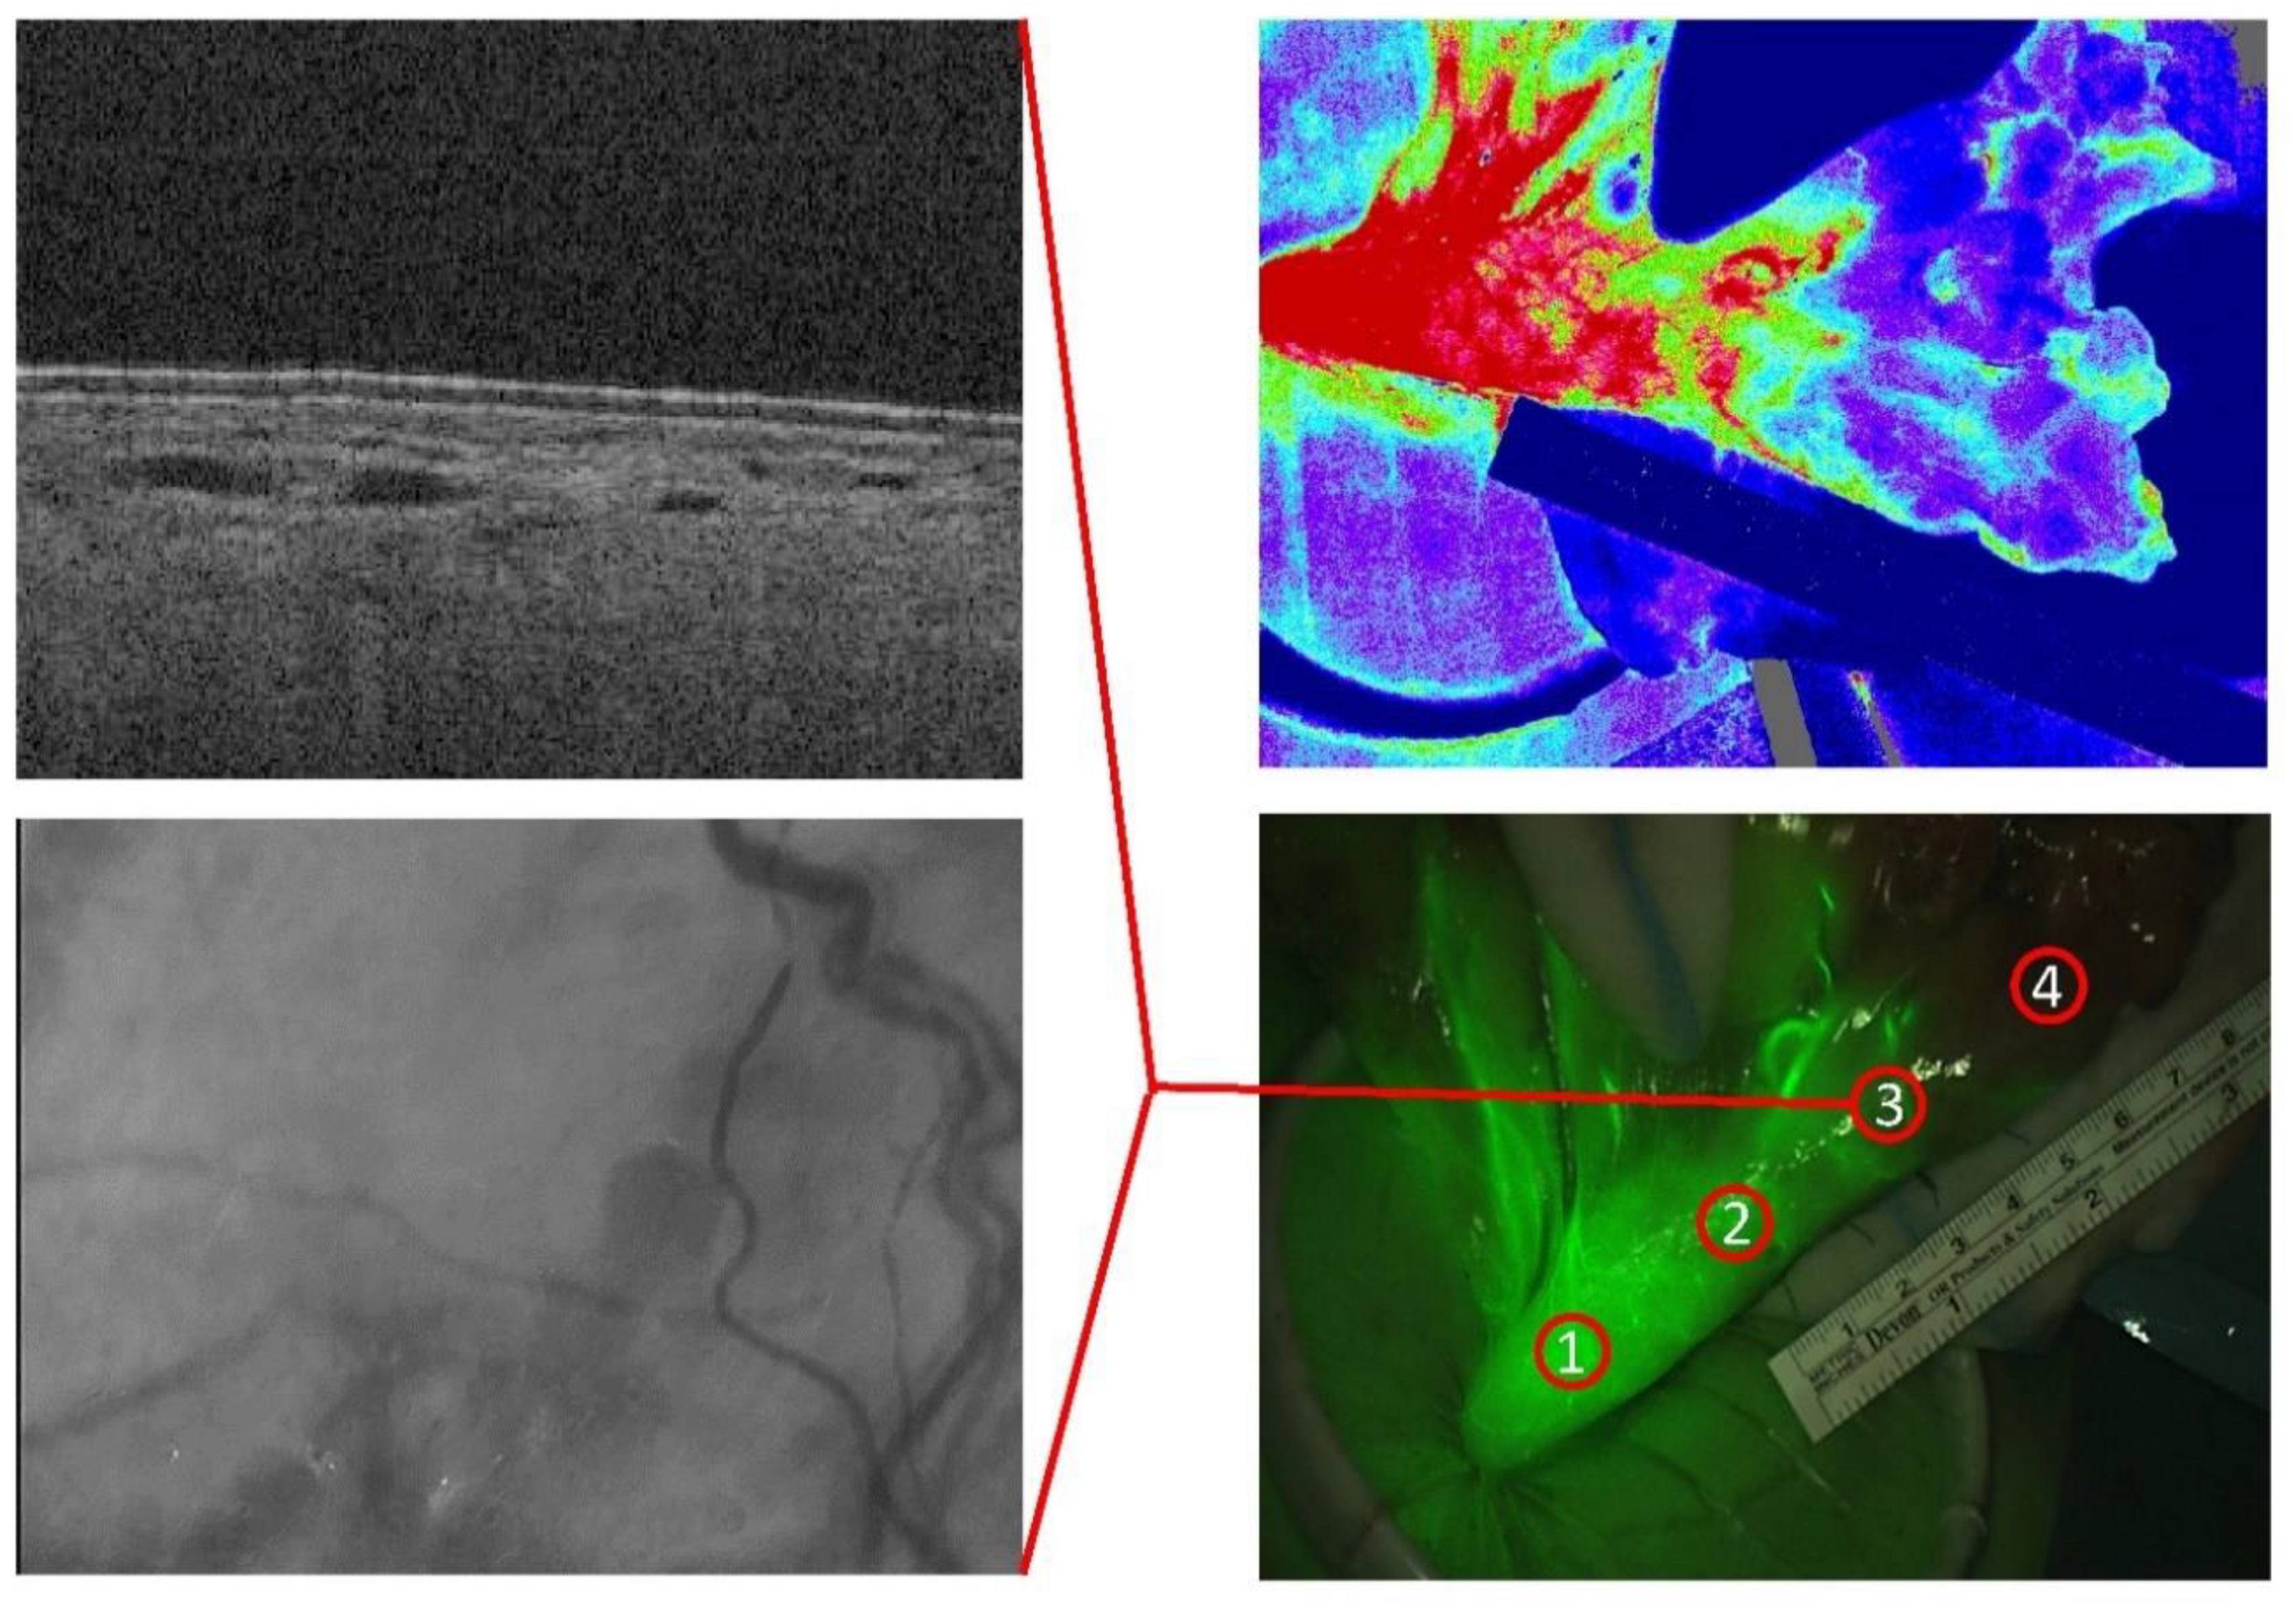

| Field of View | Depth-Resolving | Ease of Use | Real-Time | Practical Limitations | |

|---|---|---|---|---|---|

| OCT | 10 mm × 10 mm × 2.5 mm | + | Sterile sheet, probe handling | + | Motion artefacts, shadowing |

| SDF | 1 mm × 1 mm | - | Sterile sheet, tissue-contact | + | Motion artefacts, focus |

| LSCI | Wide-field ROI: ø 1 cm | - | Non-contact | + | OR lights off |

| FA | Wide-field ROI: ø 1 cm | - | Non-contact | + | Invasive (ICG injection), OR lights off * |